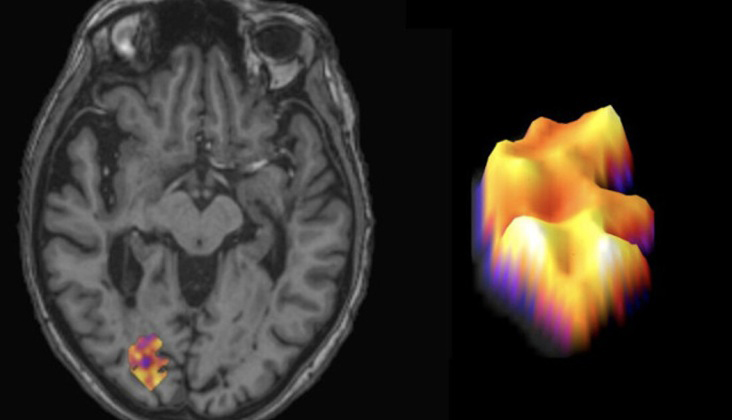

برای درک مکانیسمهای محرک ام اس پیشرونده، پژوهشگران یک مدل موشی جدید توسعه دادند که آسیب به ماده خاکستری مغز؛ بخش پردازشکننده اطلاعات در مغز را که در بیماران پیشرونده دیده میشود، تقلید میکند. ویژگی بارز این آسیب خاکستری، التهاب محصور شده در لپتومننژها leptomeninges؛ غشای نازک شبیه به پلاستیک که مغز و نخاع را احاطه کرده است. در این مدل موشی، آنها افزایش حدود ۸۰۰ برابری در یک سیگنال ایمنی به نام CXCL13 و کاهش قابل توجه سطوح پروتئین ایمنی دیگری به نامBAFF را مشاهده کردند.

با درمان این موشها با داروهای مهارکننده BTK inhibitors، پژوهشگران یک مدار مغزی را ترسیم کردند که منجر به آسیب ماده خاکستری و التهاب میشود. آن ها همچنین دریافتند که این مهارکنندهها سطوح CXCL13 و BAFF را به حالت موشهای سالم بازمیگردانند.

این نتایج باعث شد پژوهشگران فرضیهای مطرح کنند که بر اساس آن نسبت CXCL13 به BAFF میتواند نشانگر جایگزینی برای التهاب لپتومننژی باشد.

برای بررسی اعتبار یافتهها در انسان، پژوهشگران نسبت CXCL13 به BAFF را در بافتهای مغزی پس از مرگ افراد مبتلا به MS و همچنین در مایع مغزی-نخاعی گروهی از بیماران زنده مبتلا به ام اس اندازهگیری کردند. در هر دو مورد، نسبت بالای CXCL13 به BAFF با التهاب محصور شده بیشتر در مغز همراه بود.